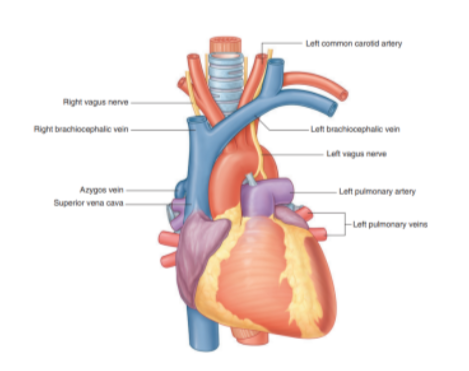

Major recognizable structures —

Thymus

Right & left brachiocephalic veins

Left superior intercostal vein

Superior vena cava

Arch of the aorta with its three large branches

Trachea

Esophagus

Phrenic nerves

Vagus nerves

Left recurrent laryngeal branch of the left vagus nerve

Thoracic duc

Other small nerves, blood vessels, and lymphatics

Right & left brachiocephalic veins

Located immediately posterior to the thymus

They form on each side at the junction between the internal jugular & subclavian veins

Left brachiocephalic vein crosses the midline & joins with the right brachiocephalic vein to form the superior vena cava

Right brachiocephalic vein begins posterior to the medial end of the right clavicle & vertically passes down

The left brachiocephalic vein begins posterior to the medial end of the left clavicle

Left superior intercostal vein

Receives the second, third, & sometimes 4th posterior intercostal veins, usually the left bronchial veins, & sometimes the left pericardiacophrenic vein

Passes over the left side of the aortic arch, lateral to the left vagus nerve & medial to the left phrenic nerve, before entering the left brachiocephalic vein

Inferiorly may connect with the accessory hemiazygos vein (superior hemiazygos vein)

Superior vena cava

Begins posterior to the lower edge of the right first costal cartilage, where the right & left brachiocephalic veins join

Terminates at the lower edge of the right third costal cartilage, where it joins the right atrium

The lower half of it is within the pericardial sac (& thus in the middle mediastinum)

Superior vena cava receives the azygos vein immediately before entering the pericardial sac & may also receive pericardial & mediastinal veins

Can be easily visualized forming part of the right superolateral border of the mediastinum on a chest radiograph

Arch of aorta

The thoracic portion of the aorta can be divided into the ascending aorta, arch of the aorta, & thoracic (descending) aorta —

Only the arch of the aorta is in the superior mediastinum

The arch extends as high as the midlevel of the sternal manubrium & is initially anterior, but later moves laterally to the trachea

From the arch we have 3 branches, each of which is crossed by the left brachiocephalic vein —

Brachiocephalic trunk

Left common carotid artery

Left subclavian artery